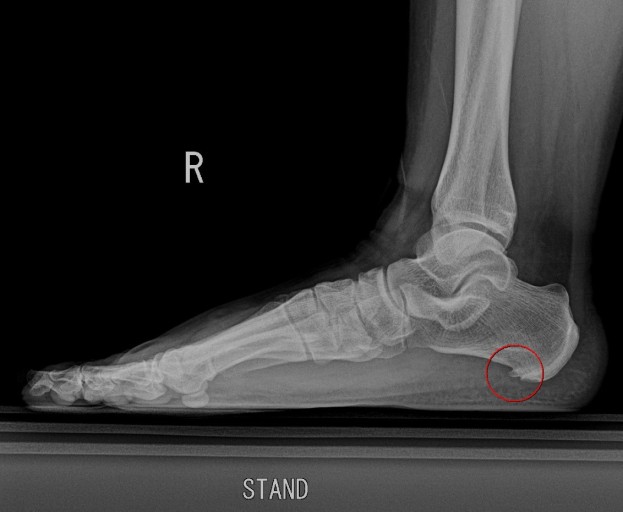

족저근막염은 우리 발바닥에 있는 족저근막 이라는 조직이 염증을 일으켜서 발생되는 병인데, 이 족저근막이 발바닥을 지탱하고 걸음걸이를 안정화 시키는 역할을 한다. 이 조직에 과도한 스트레스가 가해지면 염증이 생기고, 이게 바로 족저근막염이다.

주요 원인으로 과체중 , 잘못된 신발, 장시간 서있거나 걷기 등이 있는데, 나는 저 세가지에 모두 다 해당되었다 ㅜ 아무리 생각해봐도 발바닥이 너무 큰 과부하가 걸린게 원인인듯 하다